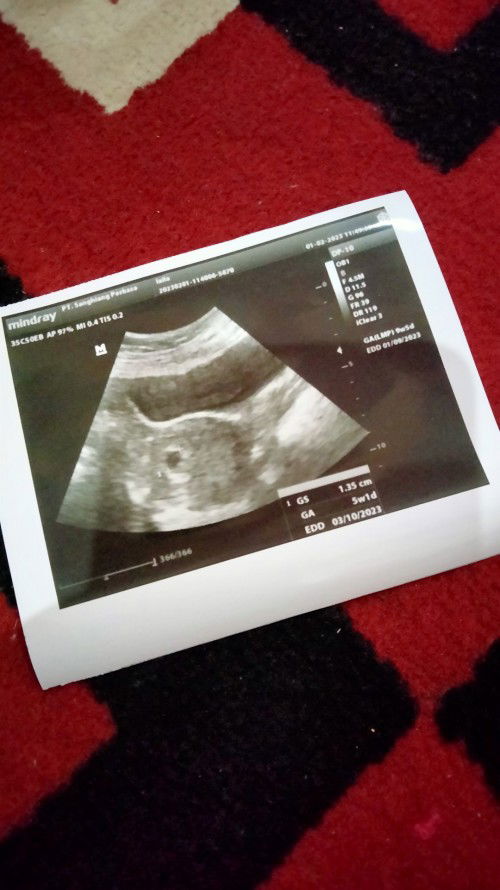

Htph 9 minggu tapi di layar usg baru berusia 5 minggu, normal gak bund?

Bund tadi saya dari usg usia di layar itu baru 5 minggu sedangkan htph itu sudah 9 minggu 5 hari. Normal gak sih bund?#bantusharing #seriusnanya